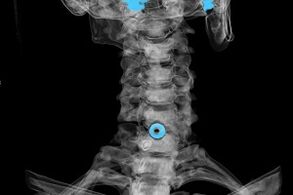

Tashxis xarakteristik alomatlar asosida tashkil etilgan, shuningdek quyidagilardan foydalanish:

- Rentgen nurlari. Bu usul, ayniqsa osteokondrozni rivojlantirishning so'nggi bosqichlarida samarasiz.

- Bachadon umurtqa pog'onasining MRI (magnit rezonanasishi). Suyak tuzilmalarini, o'tmishni, ularning o'lchamlari va rivojlanish yo'nalishini ko'rish imkonini beradigan usul.

- Kompyuter tomografiyasi. MRI ga qaraganda kamroq samarali echim, chunki churraning mavjudligi va hajmi va o'lchamini aniqlash qiyin.